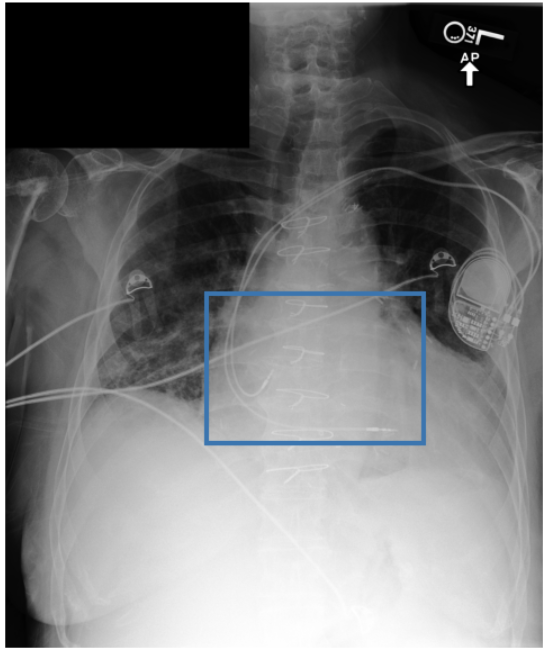

Figure 3 shows phrase grounding results for the phrase “Chronic inflammatory changes predominantly in both lung apices” on an image from PadChest-GR [11]. Both CURE and MAIRA-2 successfully identify the lung apices associated with the described findings. However, CURE’s localization is more accurate and better aligned with the phrase semantics, while MAIRA-2 provides a coarser prediction that only partially covers the relevant areas. As expected, MedGemma-4B-IT does not produce visual grounding outputs, and thus no bounding boxes are shown for this model.